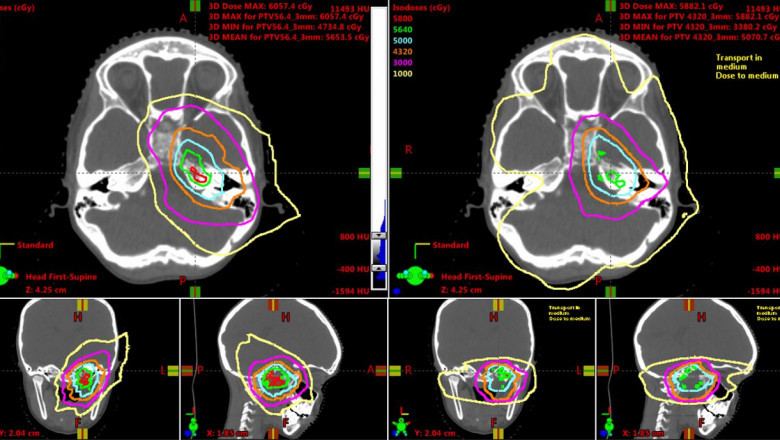

In the clinical field, proton therapy or proton radiography, is a type of radiotherapy, which utilizes a progression of protons, generally combined with an enemy of proton pillar, to illuminate influenced tissue, ordinarily to fix disease. At the point when the protons are joined with an electron, or core, they become profoundly vivacious and discharge gamma beams. These gamma beams are utilized to target explicit dangerous cells in the therapy of malignancy by creating an explosion of warmth through neutrons and/or electrons. These beams are then consumed by carcinogenic tissue to obliterate it. This proposes that development of the intensity-modulated proton therapy market is driven by high frequency of malignant growth around the world.

Intensity modulated proton therapy suggests the electromagnetic spatial control of all around surrounded light emissions of variable energy and intensity. Proton therapy was first utilized on patients experiencing bosom malignancy who had no other option, aside from carefully eliminating the entire bosom (mastectomy) to eliminate the dangerous tissue. As indicated by the American Cancer Society, in 2020, around 276,480 new instances of obtrusive bosom malignancy will be analyzed in ladies and the illness will prompt around 42,170 passings, in the U.S. The U.S. is hence expected to observe critical development in the intensity-modulated proton therapy market.